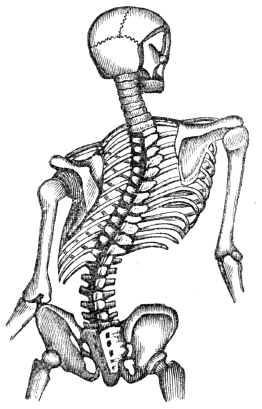

| 33. | Hygiene of the Skin, | 301 |

| 34. | Hygiene of the Skin, continued, | 311 |

| 38. | Physiology of the Nervous System, | 346 |

| 39. | Hygiene of the Nervous System, | 358 |

| 40. | Hygiene of the Nervous System, continued, | 368 |

| 41. | The Sense of Touch, | 378 |

| 42. | Anatomy of the Organs of Taste, | 384 |

| 43. | Anatomy of the Organs of Smell, | 389 |

82. The TRUNK has fifty-four bones—twenty-four Ribs; twenty-four bones in the Spi´nal Col´umn, (back-bone;) four in the Pel´vis; the Ster´num, (breast-bone;) and the Os hy-oid´es, (the bone at the base of the tongue.) They are so arranged as to form, with the soft parts attached to them, two cavities, called the Tho´rax (chest) and Ab-do´men.

80. How many bones in the ear? 81. How many bones in the face? What is their use? Explain fig. 8. 82–94. Give the anatomy of the bones of the trunk. 82. How many bones in the trunk? Name them. What do they form by their arrangement?

83. The THORAX is formed by the sternum in front; the ribs, at the sides; and the twelve dorsal bones of the spinal column, posteriorly. The natural form of the chest is a cone, with its apex above; but fashion, in many instances, has nearly inverted this order. This cavity contains the lungs, heart, and large blood-vessels.

87. The SPINAL COLUMN is composed of twenty-four pieces of bone. Each piece is called a vert´e-bra. On examining one of the bones, we find seven projections, called processes; four of these, that are employed in binding the bones together, are called articulating processes; two of the remaining are called the transverse; and the other, the spinous. The last three give attachment to the muscles of the back.

88. The large part of the vertebra, called the body, is round and spongy in its texture, like the extremity of the round bones. The processes are of a more dense character. The projections are so arranged that a tube, or canal, is formed immediately behind the bodies of the vertebræ, in which is placed the me-dul´la spi-na´lis, (spinal cord,) sometimes called the pith of the back-bone.

89. Between these joints, or vertebræ, is a peculiar and highly elastic substance, which much facilitates the bending movements of the back. This compressible cushion of cartilage also serves the important purpose of diffusing and diminishing the shock in walking, running, or leaping, and tends to protect the delicate texture of the brain.

86. How are the ribs united to the sternum? 87. Describe the spinal column. 88. Give the structure of the vertebra. Where is the spinal cord placed? 89. What is placed between each vertebra? What is its use?

90. Another provision for the protection of the brain, which bears convincing proof of the wisdom and beneficence of the Creator, is the antero-posterior, or forward and backward curve of the spinal column. Were it a straight column, standing perpendicularly, the slightest jar, in walking, would cause it to recoil with a sudden jerk; because, the weight bearing equally, the spine would neither yield to the one side nor the other. But, shaped as it is, we find it yielding in the direction of the curves, and thus the force of the shock is diffused.

91. The PELVIS is composed of four bones; the two in-nom-i-na´ta, (nameless bones,) the sa´crum, and the coc´cyx.

93. The SACRUM, so called because the ancients offered it in sacrifices, is a wedge-shaped bone, that is placed between the innominata, and to which it is bound by ligaments. Upon its upper surface it connects with the lower vertebra. At its inferior, or lower angle, it is united to the coccyx. It is concave upon its anterior, and convex upon its posterior surface.